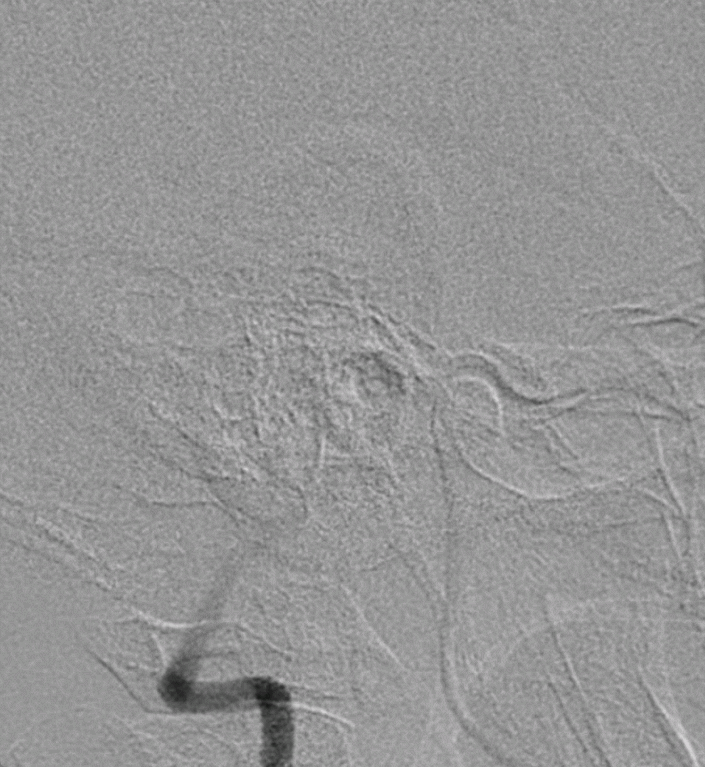

正侧位造影

通过3D工作位测量出基底动脉瘤瘤颈最宽处:6.5mm;载瘤动脉尺寸:近端直径3.7mm,远端直径4.2mm。